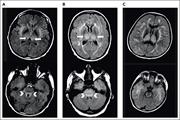

Bone marrow reticulin staining from the hMPLW515L adoptive transfer mouse model of bone marrow fibrosis treated with ruxolitinib. See the article by Dunbar et al on page 2508.